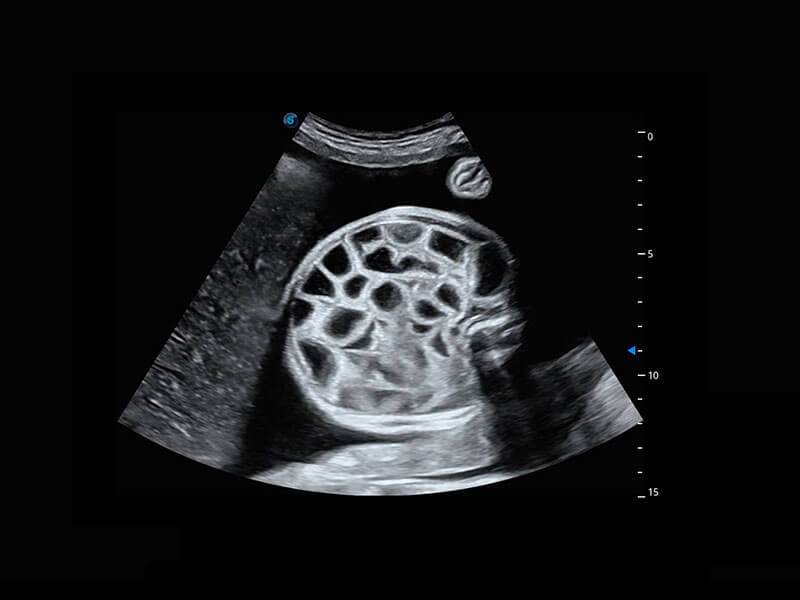

中晚孕筛查

P60提供简单易学易用的高端诊断工具,为您中晚孕筛查提供快速清晰的解剖信息。

S-Fetus能够助您在实时扫查过程中自动识别标准切面、自动测量并录入报告。一个按键,即可快速、高效地获取胎儿生理指标,简化您的产科检查操作。